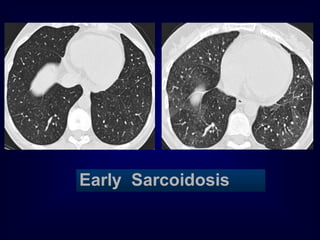

Early Sarcoidosis

Sarcoidosis

•

Multi system granulomatous disease

• Unknown etiology

90% of patients with sarcoidosis have

chest changes

Bilateral hilar and mediastinal adopathy

Interstitial disease  lymph nodes

Alveolar pattern simulating acute

inflammatory disease]

Cavitation, atelectasis, effusion (rare)